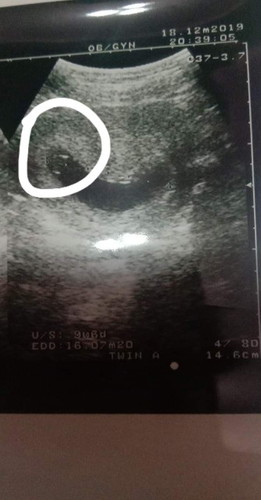

การตั้งครรถ์ค่ะ

แบบนี้มีโอกาสท้องลมมั้ยคะ